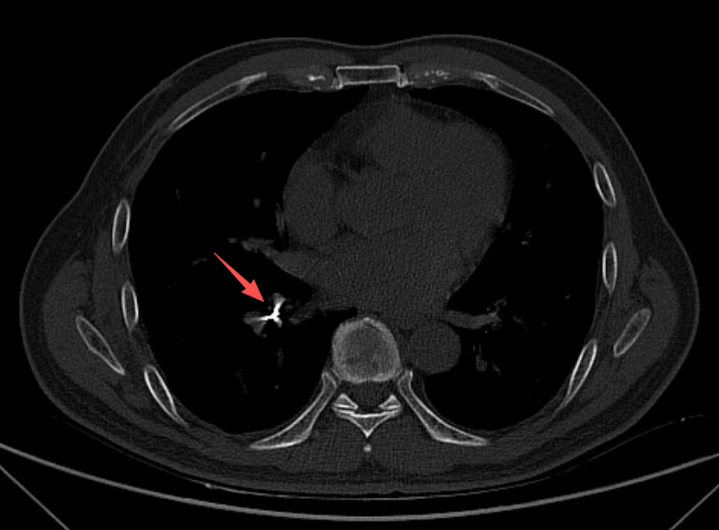

随后,诊所牙医随同男人到北海市东谈主民病院就诊,经CT查验,在患者右下肺支气管内发现存异物存留,便要害收入呼吸与危重症医学科病房。

经证据,取出的异物恰是用于根管休养的机扩针,长约2厘米,针的一头圆滑、一头细长而厉害。